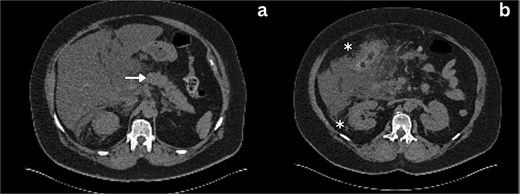

Following a brief clinical response to the initial conservative management for 24 hours, the patient started deteriorating and developed generalized peritonitis with worsening of inflammatory markers (C-reactive protein escalated to 438 mg/l). Consequently, she underwent an emergency diagnostic laparoscopy as the cause of peritonitis was not clear. Intraoperatively, it was observed that there was free bile in the peritoneal cavity, more so around the liver and the right paracolic gutter. There was also a bile collection behind the right colon and hepatic flexure of the colon, raising the possibility of a retroperitoneal source. The hepatic flexure of the colon was mobilized to assess the source of the leak. No obvious ongoing leak was noticed. As a precautionary measure, an Upper GI endoscopy was conducted intra-operatively to rule out any gastroduodenal perforation, as no obvious source of bile leak was seen from the biliary tree. This revealed the presence of bile in the stomach and confirmed normal anatomy up to the third part of the duodenum. The remaining intra-abdominal organs appeared unremarkable. Thorough peritoneal lavage was given, and 22 Fr abdominal drains were placed in the subhepatic, para-hepatic space, and pelvis, respectively, as the source of leak was not found. The following day, an endoscopic retrograde cholangiopancreatography (ERCP) was performed, which identified a small leak around the area of the cystic duct stump (Fig. 3). In response, a 5 cm-sized 7 Fr double pigtail stent was inserted into the CBD. A post-ERCP CT scan was performed to evaluate the contrast leak. The CT imaging revealed an extraluminal contrast leak originating from a defect in the posterior CBD (Fig. 4). Notably, the cystic duct stump remained intact and anterior, establishing the diagnosis of Spontaneous biliary leak from the CBD.

Axial and coronal section CT imaging revealing contrast leak from the bile duct; a) Contrast leak from the posterior aspect of CBD (arrow). b) Contrast extravasation into the subhepatic drain (arrow).